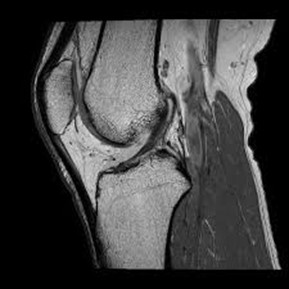

• conditions involving musculoskeletal system including the knee, shoulder, ankle, wrist and elbow as well as ligament, meniscus and rotator cuff tears

• injuries, tumors, and degenerative disorders of bone joints, spine, ligaments, meniscus in the skeletal muscular structure of the body